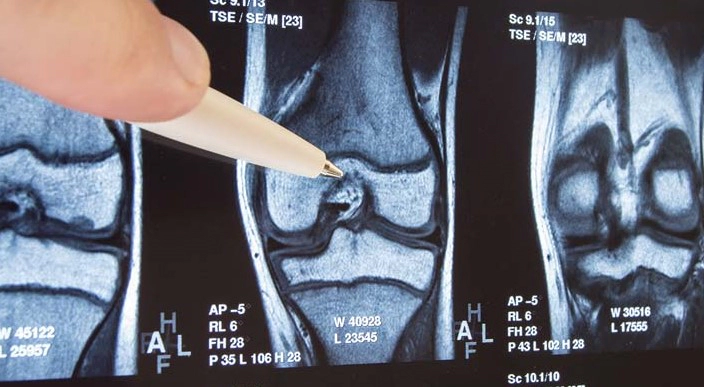

무릎 관절염은 무릎 관절의 염증과 관련된 질환으로, 연골 손상, 관절 주위의 연조직의 염증, 뼈의 변형 등 다양한 원인이 있을 수 있습니다.

무릎 관절염이 진행되면서 연골이 닳거나 뼈가 변형되면 관절의 움직임이 제한될 수 있습니다. 이로 인해 일상 생활에서의 움직임이 불편해지고, 무릎을 완전히 굽히거나 펴기 어려워질 수 있습니다.

무릎 관절을 움직일 때 뼈가 서로 부딪히거나 마찰로 인해 딱딱한 소리가 날 수 있습니다. 이 소리는 무릎 관절의 연골이 닳거나 뼈가 변형된 결과일 수 있습니다.

무릎 관절염이 심해지면 뼈의 변형이 발생할 수 있습니다. 이로 인해 무릎 관절이 비정상적인 모양을 갖게 되며, 심한 경우에는 무릎을 완전히 굽히거나 펴지 못하게 됩니다.